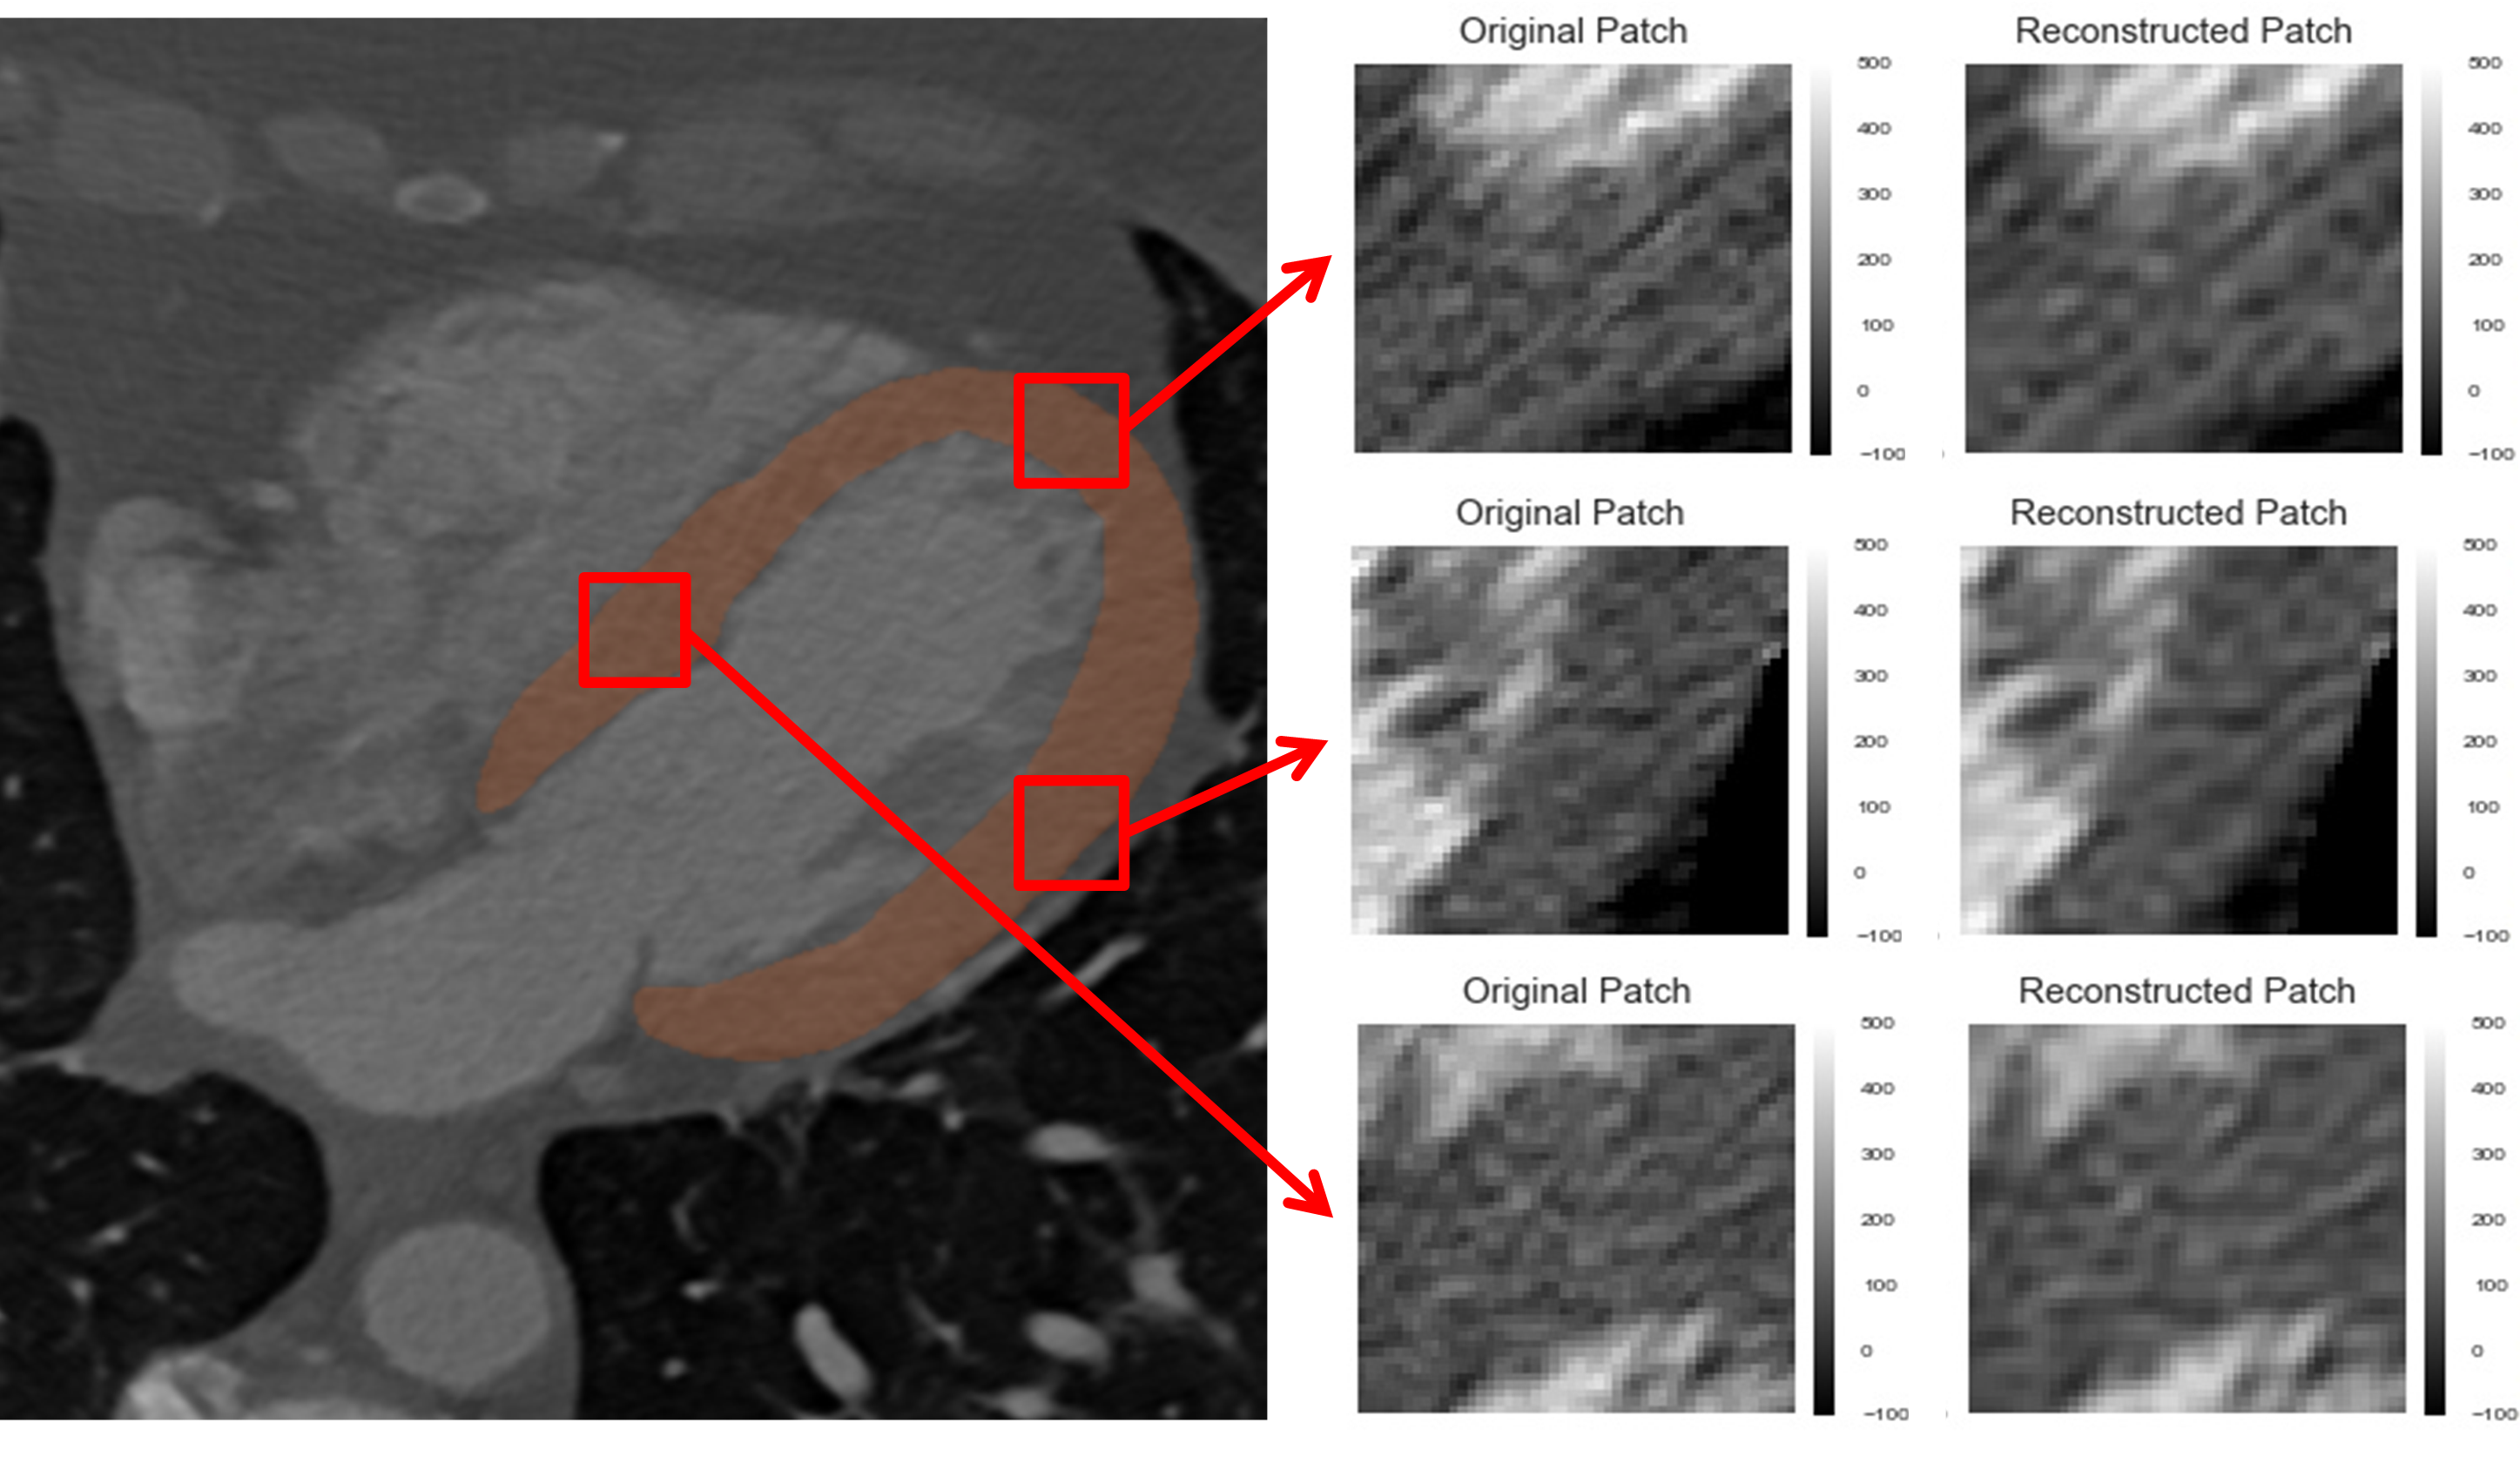

To extract encodings and features of the LV myocardium, the pre-trained multiscale CNN and CAE described in [18] were employed in all 126 CCTA scans to segment and encode the LV myocardium, respectively. Fig. 5 illustrates a segmented LV myocardium and three randomly selected LV myocardium axial patches that were encoded and thereafter reconstructed back.

Refer to caption

Figure 5: Left: An example of an axial view of an CCTA scan, with the automatically segmented LV myocardium (red overlay) using the pre-trained multiscale CNN. Right: Within the segmented LV myocardium, 3 randomly selected myocardial image patches (Original) are encoded and then reconstructed (Reconstructed) by the pre-trained CAE, as presented in [18].